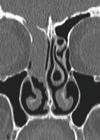

In the first of this two-part series, Martyn Barnes and colleagues discussed indications for functional endoscopic sinus surgery (FESS), the surgical objectives and techniques, patient expectations and the risks of surgery [1]. In this second and final part, the authors...

In the first of a two-part series, Martyn Barnes and colleagues discuss indications for functional endoscopic sinus surgery (FESS), the surgical objectives and techniques, patient expectations and the risks of surgery. In part two, the authors will discuss how to...